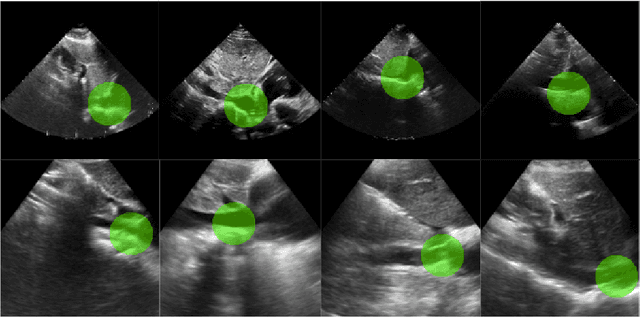

Abstract:Ultrasound imaging of the heart (echocardiography) is widely used to diagnose cardiac diseases. However, obtaining an echocardiogram requires an expert sonographer and a high-quality ultrasound imaging device, which are generally only available in hospitals. Recently, AI-based navigation models and algorithms have been used to aid novice sonographers in acquiring the standardized cardiac views necessary to visualize potential disease pathologies. These navigation systems typically rely on directional guidance to predict the necessary rotation of the ultrasound probe. This paper demonstrates a novel AI navigation system that builds on a decision model for identifying the inferior vena cava (IVC) of the heart. The decision model is trained offline using cardiac ultrasound videos and employs binary classification to determine whether the IVC is present in a given ultrasound video. The underlying model integrates a novel localization algorithm that leverages the learned feature representations to annotate the spatial location of the IVC in real-time. Our model demonstrates strong localization performance on traditional high-quality hospital ultrasound videos, as well as impressive zero-shot performance on lower-quality ultrasound videos from a more affordable Butterfly iQ handheld ultrasound machine. This capability facilitates the expansion of ultrasound diagnostics beyond hospital settings. Currently, the guidance system is undergoing clinical trials and is available on the Butterfly iQ app.